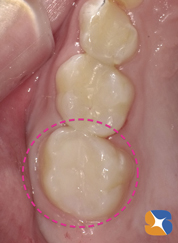

小学生。夏休み終盤の8/29。主訴は、上の奥歯「学校検診で虫歯が見つかった。最近、甘い物を食べると痛い。遠方のため、早く終わらせたい」でした。

更に「以前、下の奥歯に銀歯を詰めた時、しばらく痛みが続いたので、今回は痛みの少ない(素材の)詰め物でお願いします」が親御様からの要望でした。その結果、セラミックの詰め物を装着することに決まりました。

セラミックなら金属と異なり、熱が伝わりにくいため、冷たさや熱さに対して痛みが少ないからです。また、院内でDr自身が製作するため、噛み合わせを考慮したセラミックの詰め物が、治療開始から2時間後には治療が終わっていることもメリットの一つです。